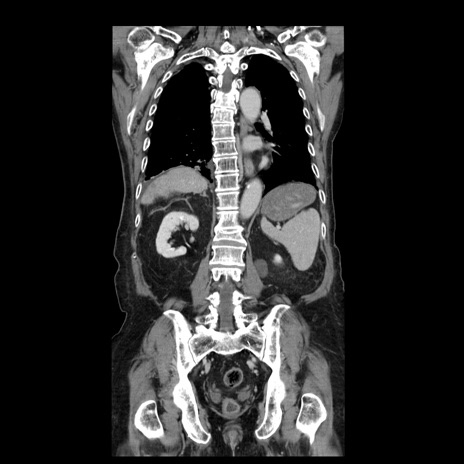

症例21(冠状断像)

【症例】70歳代男性

【主訴】腹痛

【現病歴】肝硬変・肝細胞癌にてかかりつけの方。約9時間前に食後より腹痛出現。症状が徐々に増悪し、嘔吐出現したため来院。

【既往歴】肝硬変、肝細胞癌(RFA、TACE後)

【身体所見】意識清明、表情苦悶様、BT 36℃、BP 129/78mmHg、P 88bpm、SpO2 97%(RA)、右上腹部から心窩部にかけて圧痛あり、反跳痛なし、筋性防御あり。

【データ】WBC 5800、CRP 0.16